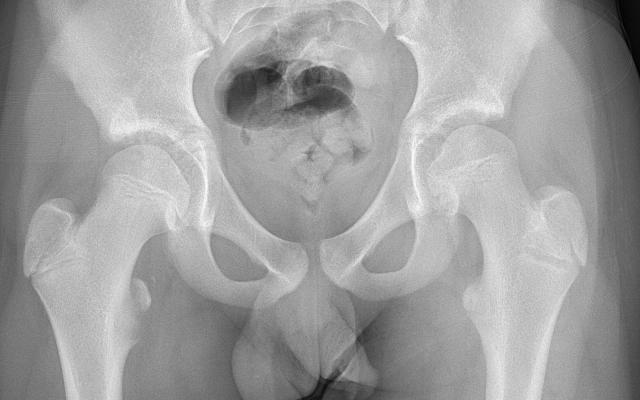

Dit artikel is alleen beschikbaar als PDF.Lees de PDF Artikelinformatie Online verschenen op 13 mei 1957 Citeer dit artikel als Ned Tijdschr Geneeskd. 1957;101:2172 Heb je nog vragen na het lezen van dit artikel? Check onze AI-tool en verbaas je over de antwoorden. ASK NTVG Ook interessant Beeldquiz Plotselinge pijn in de lies Diagnose in beeld Plotselinge pijn in de lies Mededelingen Plotselinge dood Meer gerelateerd … Reacties Login om een reactie te plaatsen